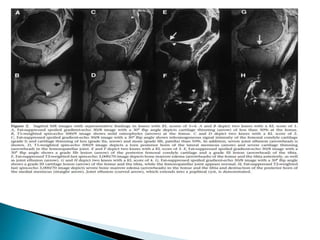

 RADIOLOGICAL FEATURES:

◦ CARTILAGE LOSS

◦ SUBCHONDRAL SCLEROSIS

◦ CYSTS

◦ OSTEOPHYTES